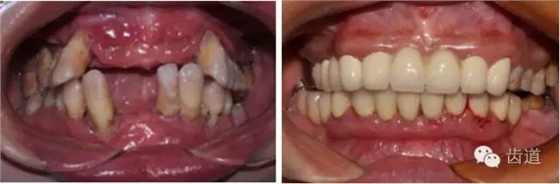

1、口腔衛(wèi)生狀況及局部刺激物(牙菌斑、牙石,不良修復體)

牙石及不良修復體

2、牙齦

(顏色、形狀、質地、退縮、BOP、PD、附著齦)